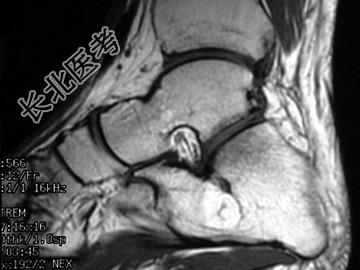

- 单项选择题男,33岁, 无明显症状,结合图像, 最可能的诊断是 ( )

A、骨囊肿

B、骨脓肿

C、未见异常

D、骨內脂肪瘤

E、血管瘤